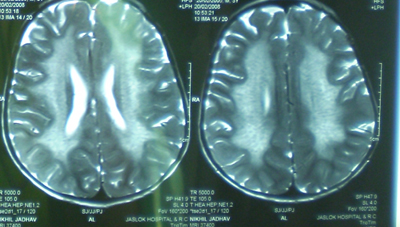

This 4 years old boy presented with frequent falls and regression of previously attained milestones. On examination, he had optic atrophy and spasticity.

Metachromatic leukodystrophy. Metachromatic leukodystrophy {MLD, also called Arylsulfatase A deficiency} is a lysosomal storage disease. Four types of MLD occur with varying ages of onset and courses {ie, late infantile, early juvenile, late juvenile, adult}. All forms of the disease involve a progressive deterioration of motor and neurocognitive function. Patients with the late infantile form are usually aged 4 years or younger and typically present initially with gait disturbances, loss of motor developmental milestones, optic atrophy, and diminished deep tendon reflexes. In addition, progressive loss of both motor and cognitive functions is fairly rapid, and death results within approximately 5 years after the onset of clinical symptoms.